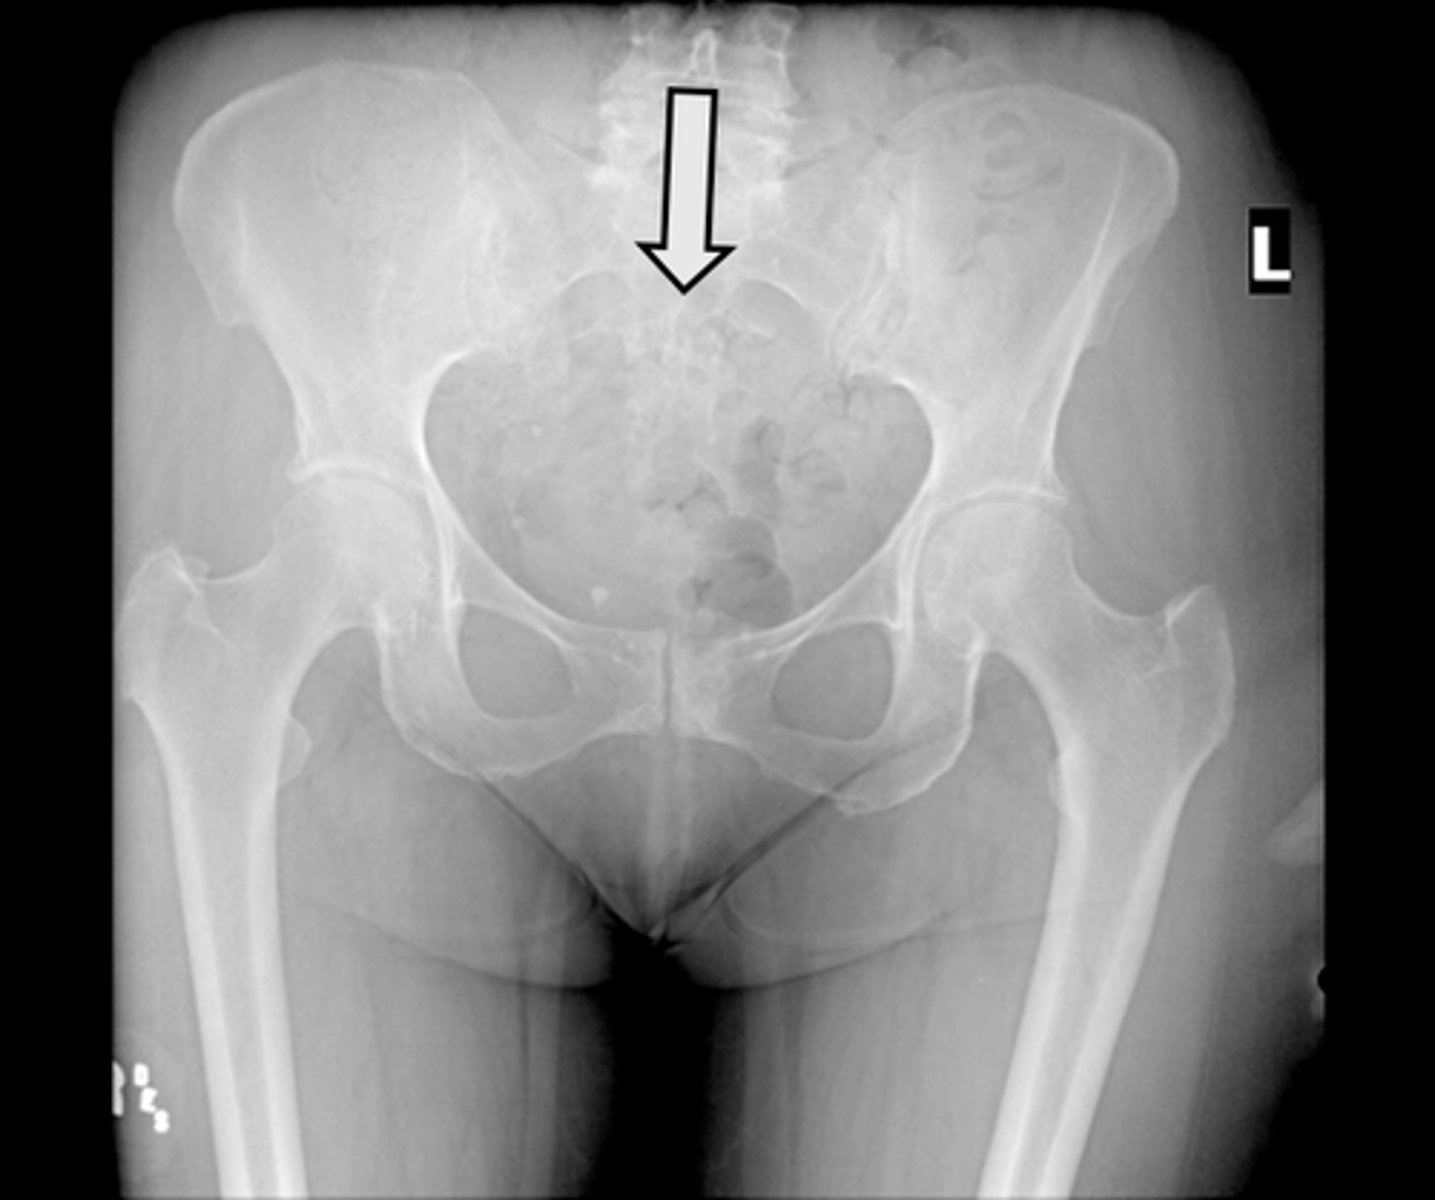

AP pelvis

What is the image?

<p>What is the image?</p>

Acetabulum

What is indicated in the image?

<p>What is indicated in the image?</p>

Body of L4

Epiphysial plate

Femoral head

Hip joint

Ilium

Ischial spine

Ischial tuberosity

Nonfused greater trochanter

Obturator foramen

Pubic symphysis

Sacroiliac joint

Sacrum